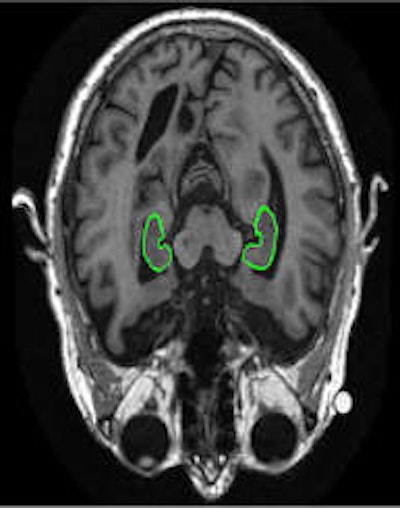

PredictAD aims to extract biomarkers from heterogeneous patient data and integrate them for objective and evidence-based diagnostics. For example its reasearch team is exploring how MRI can be used to measure atrophy in the mediotemporal lobe, which is recognized as a hallmark of Alzheimer's.

To meet this need, the PredictAD team has developed tools for measuring the size of the hippocampus, the atrophy rate of the hippocampus, and two approaches based on comparing patient data with previously diagnosed cases available in large databases. PET is also being studied in the project. A novel tracer developed recently especially for diagnostics of Alzheimer's disease provides promises for very early diagnosis of the disease.